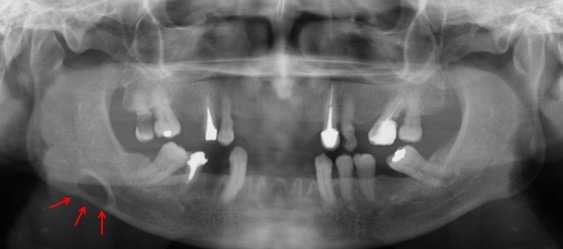

Paciente de sexo femenino, 60 años de edad, asintomática, referida al Centro Imagenológico para el estudio por imágenes previo a la colocación de implantes. A la evaluación en la radiografía panorámica (Figura 1) se evidenció la presencia de una imagen radiolúcida localizada en la zona antegonial del lado derecho, por debajo del canal mandibular, de límites definidos y bordes corticalizados. Al estudio mediante TCHC, se observó en los cortes axial y coronal, una concavidad bien delimitada, dependiente de la tabla ósea lingual que condicionaba el adelgazamiento de la cortical vestibular (Figura 2a- b). En el corte sagital (Figura 2c) y reconstrucciones 3D (Figura 2d) se evidenció la imagen hipodensa bien delimitada en la región antegonial, cursando con adelgazamiento de la basal mandibular, sin afectar la trayectoria del canal mandibular. La imagen muestra signos tomográficos compatibles con COS Tipo II.

Figura 1 FIGURA 1. Radiografía panorámica donde se observa imagen radiolucida de forma ovoide, corticalizada, localizada en región antegonial derecha (Flechas).